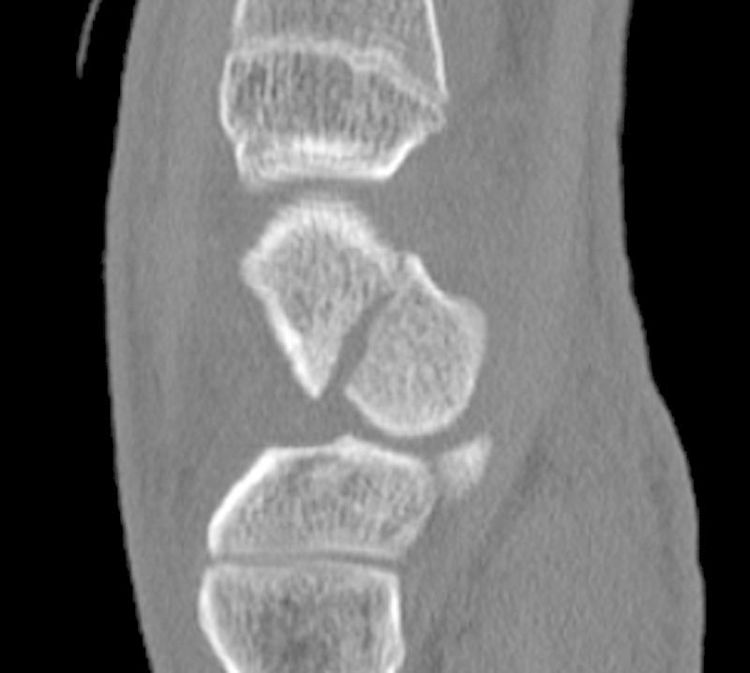

Source: kutumbhhny.pages.dev Fracture du scaphoïde et ses complications L'institut de chirurgie de la main de l'ouest parisien , Le tiers distal devrait guérir en 6-8 semaines, le tiers moyen en 8-12 semaines et le tiers proximal en 12-24 semaines Comme l'apport sanguin est nécessaire pour guérir une fracture, la guérison du scaphoïde prend souvent beaucoup de temps (quelques mois)

Source: teegraphbed.pages.dev Fracture du scaphoïde et ses complications L'institut de chirurgie de la main de l'ouest parisien , Le temps de reconsolidation de cet os assez mal vascularisé est long et varie en fonction des différents types de fractures et du traitement mis en place Le délai de consolidation varie en fonction de la localisation de la fracture

Source: realysisqle.pages.dev Fracture du scaphoïde Paris Clinique Docteur Gilles Cohen , Le tiers distal devrait guérir en 6-8 semaines, le tiers moyen en 8-12 semaines et le tiers proximal en 12-24 semaines En général, on estime que l'os prendra entre 8 à 12 semaines avant de guérir.